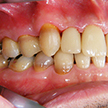

5. 初診時右側

八重歯を中心とした叢生が顕著です。その周囲のみが既にクラウンとなっており、不適合が目立ちます。